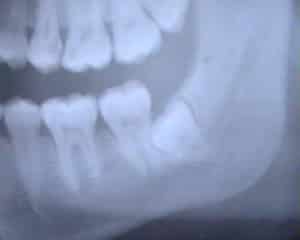

Неполное формирование корней чаще всего относится к восьмым молярам. Обычно коронка восьмых моляров формируется внутри десны к 12 годам, когда верхняя часть моляра уже полностью развита. Однако корни остаются недоразвитыми. Их формирование завершается к 25 годам, когда моляр уже частично прорезался. На рентгеновском снимке крайних моляров видно, что корень маленький и находится в стадии формирования.